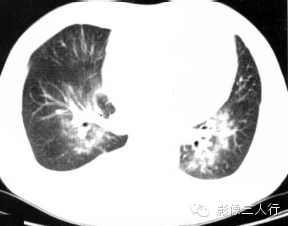

【报告范例2】

报告书写:胸廓对称,两肺下叶磨玻璃密度和肺实变影像,双侧对称,呈“蝶翼征”。双侧肺门不大,纵隔居中,其内未见肿大的淋巴结。心脏大小正常,胸壁软组织未见异常(图2)。

图2肺泡性肺水肿